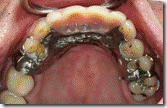

患者A先生

上顎 正面 下顎

患者B小姐

以上兩位患者口內狀況非常複雜,要制定一個好的治療計畫,

不只要考慮到患者的牙齒條件,

還要顧及患者意願、時間、金錢、評估可獲得的結果等等。

所以像這類型的Case 醫師通常在初步的溝通後會先做出一兩個不同的治療計畫,

再和患者解釋,了解患者接受程度。